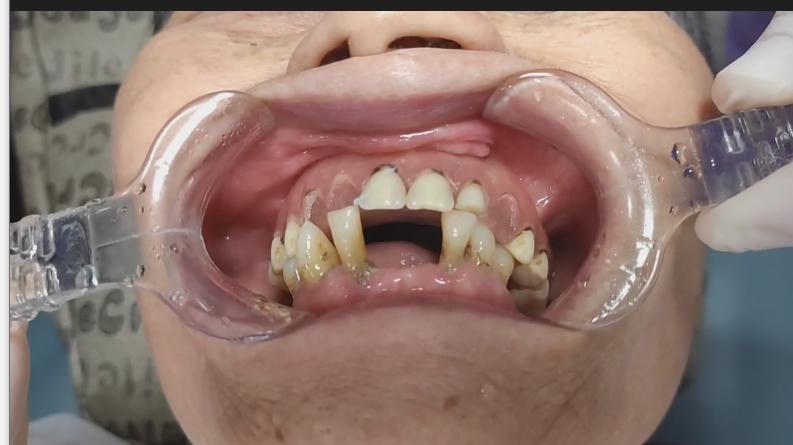

不久前,六十七岁的陈大妈因戴上颌活动假牙吃东西疼、假牙在口腔里戴不牢,在女儿的陪同下来到浙二医院口腔修复科,找到董研主任诊疗。

陈大妈口内上颌可摘义齿已经佩戴了十余年,虽然多颗人工牙脱落但咀嚼时没有不舒服,所以很多年没去看医生复诊。最近一年多,她发现自己的上牙床长出了很多“肉赘”。开始时不疼就没在意,而最近一段时间假牙就根本不能用了。戴着义齿吃东西牙床就痛,而且义齿也戴不牢,吃东西会脱落,已经影响到大妈的饮食和身体健康。

经董研主任医师的仔细问诊和口腔检查,发现陈大妈口腔里那些“肉赘”是不良增生物,需要马上切除再考虑重新制作义齿。后经病理检查证实确是良性肿物。

陈大妈这个病例告诉大家:由于牙齿缺失后牙槽骨终生不断的吸收,可造成可摘义齿的基托边缘变长从而压迫周围软组织,导致牙槽黏膜的增生有时甚至恶变。因此, 戴义齿应遵医嘱定期复查。